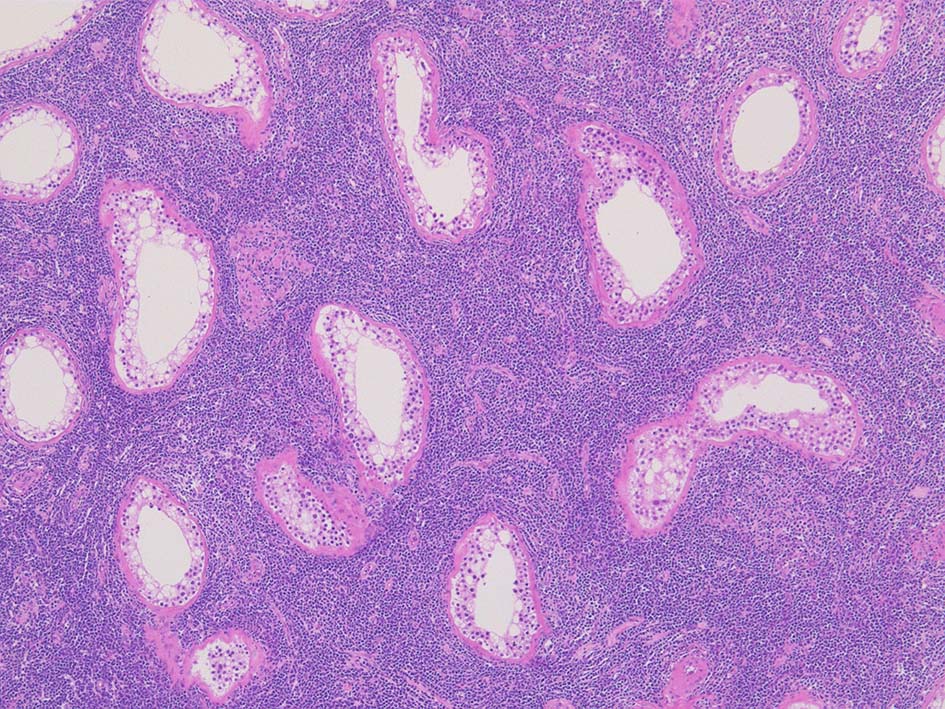

精細管の多くがスペアされ, 間質にlymphoid cellsが密に浸潤している. わずかな精細管に浸潤が認められ萎縮や破壊像が認められる. 精細管において Lymphoepithelial lesion(LEL)に似た所見がある.

類円形/多稜形の核をもつN/C比大の細胞. 粗大なクロマチンが増加, 核小体は不明瞭. DLBCLに認められるcentroblasts/ immunoblastsの細胞所見と異なる.